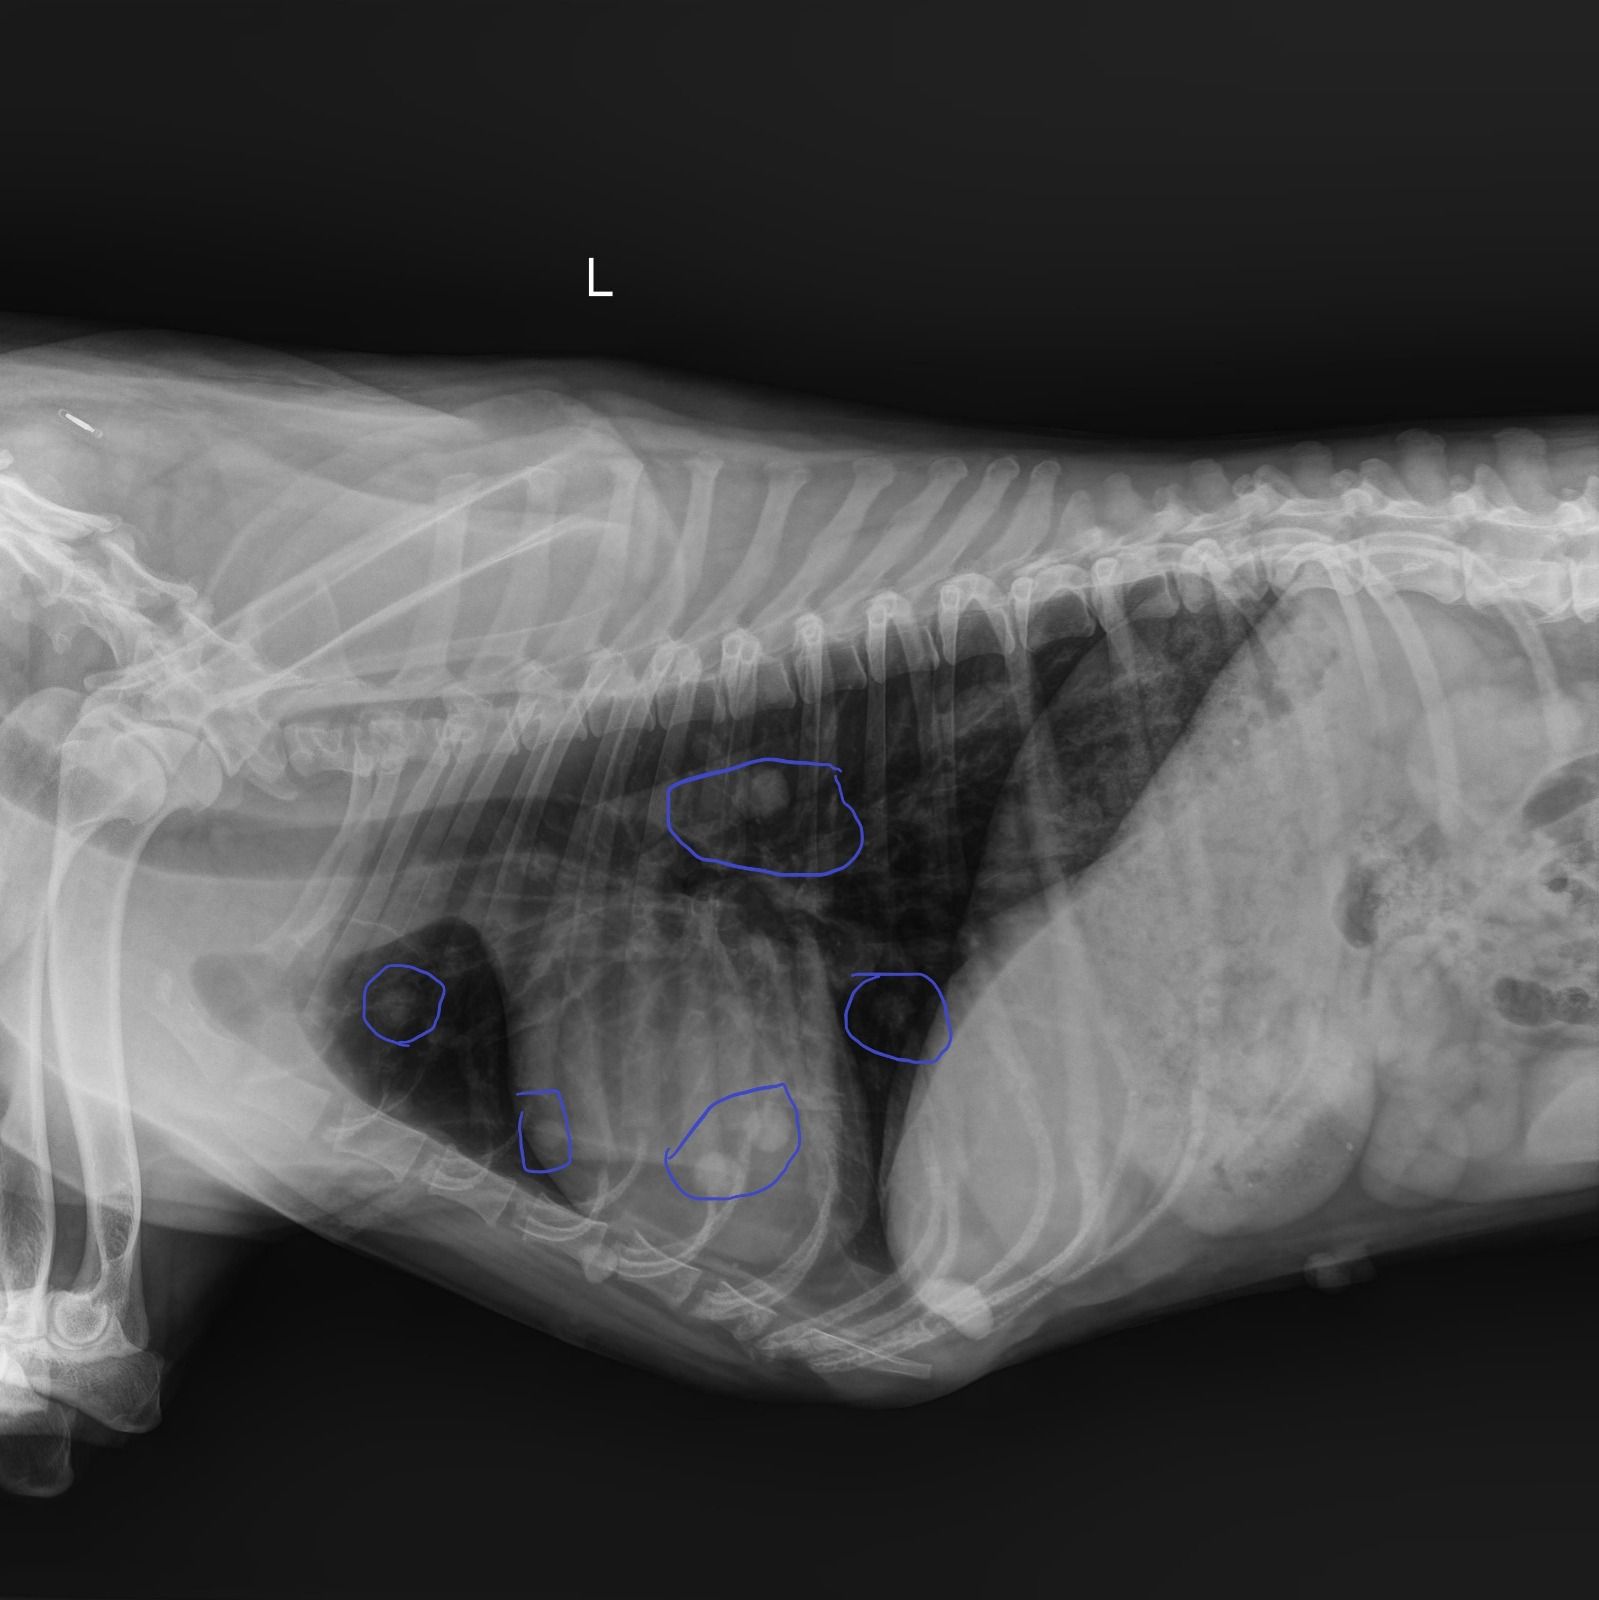

Die Ergebnisse der Röntgenaufnahme sind leider nicht so gut! 😢

Gary hat eine Hüftgelenksdysplasie an beiden Hinterbeinen. Die Köpfe beider Oberschenkelknochen befinden sich außerhalb der korrekten Position, da die Hüftpfanne an anatomischer Tiefe verloren hat. Die Knochen sind ausgerenkt, und können nur auf chirurgischem Wege korrigiert werden, entweder durch Ersatz der Oberschenkelköpfe (dies wird von einem Kollegen in Athen durchgeführt) oder durch Entfernung der Köpfe und die Bildung eines Pseudogelenks (zwei Operationen im Abstand von 3 Monaten, Kosten 650€ pro Operation in unserer Klinik). Da Gary wirklich leidet, müssen diese Operationen sein, also 1300 € kommen hier mindestens auf uns zu.

Dafür suchen wir Paten für Gary